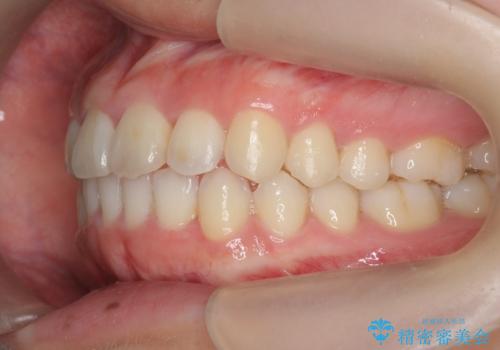

- ねじれの目立つ前歯の見た目を改善したいと矯正治療を希望され来院されました。

がたつきの改善をマウスピース矯正インビザラインで行っていきます。

ガタつきの改善はもちろん、歯列全体のアーチも放物線状にきれいに排列し審美性を向上させることができました。